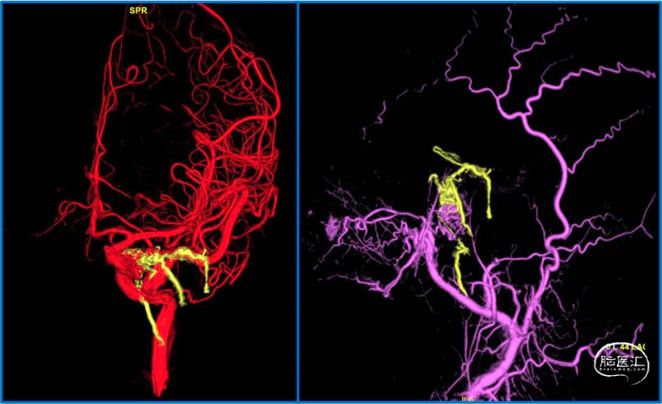

典型病例

蝶顶窦旁DAVF属于Borden III型,需要积极外科治疗。

蝶顶窦旁DAVF,可吸引前和中颅窝硬膜的所有动脉参与供血。其中颈内动脉及其分支的供血可以使用显微外科技术阻断;颈外动脉的供血动脉可以使用介入栓塞技术阻断。

引流静脉是否引流进入海绵窦,决定DAVF诊断为“颈动脉-海绵窦动静脉瘘”还是“蝶顶窦旁DAVF”。

静脉的引流路径决定患者静脉高压的临床表现,预后风险,治疗方案。